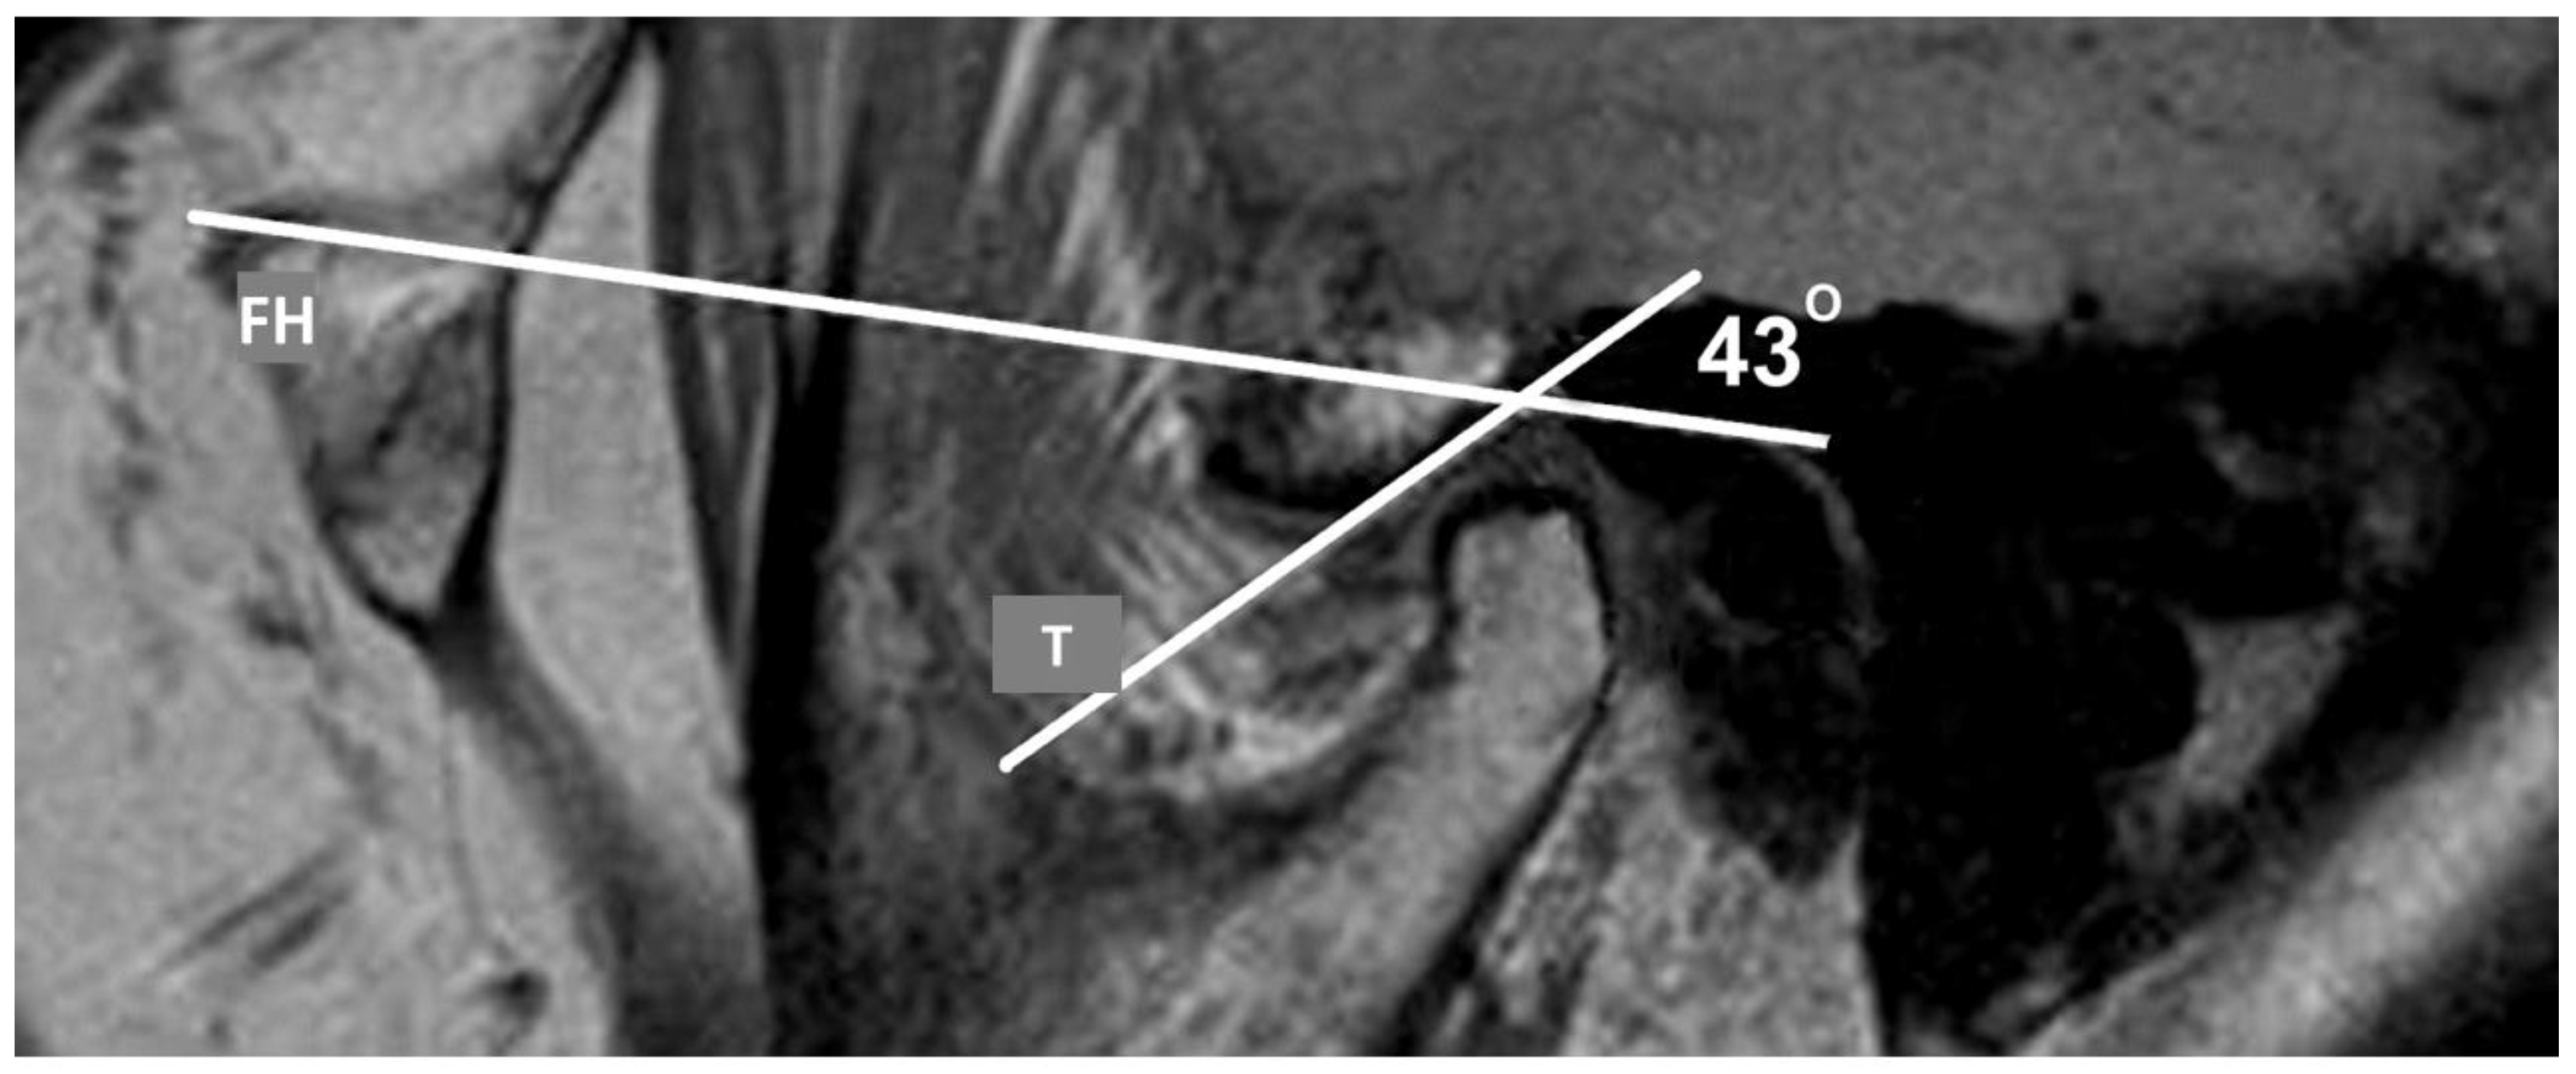

2.4. Analysis of TMJ